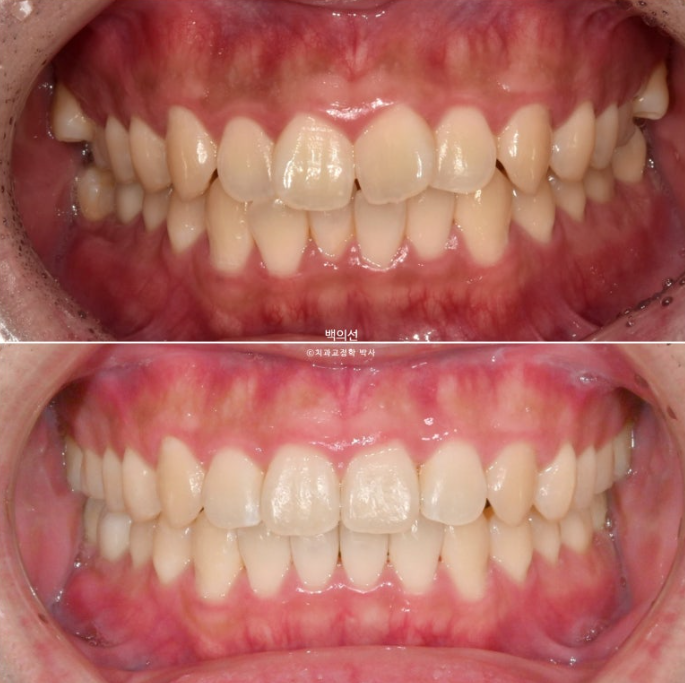

치료 전 후 비교해보겠습니다.

좌 치료 전 / 우 치료 후

24.01~25.05

총 치료기간은 1년 4개월이며 인비절라인으로 치료한 기간은 9개월 입니다.

앞니 돌출의 개선

깔끔해진 미소가 돋보이네요.